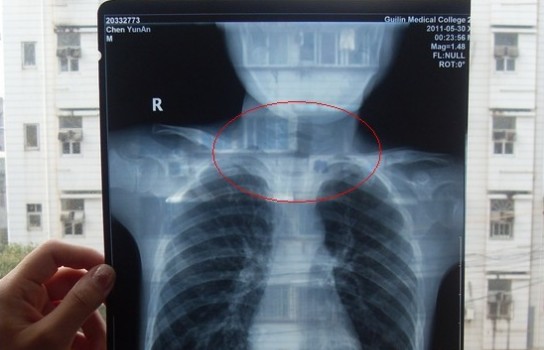

胸部正位X光片圖

2011年5月29日下午,陳先生的兒子安安出現(xiàn)嘔吐、肚子疼痛等癥狀。陳先生立即將兒子送往醫(yī)學(xué)院附院,根據(jù)醫(yī)生開出的會診單,分別對安安做了腹部立臥位2次和胸部正位1次共3次X光片檢查、診斷。醫(yī)生看X光片后排除了腸梗阻病因,判斷是闌尾炎。經(jīng)過治療,不久安安身體痊愈。

可是,陳先生的一次偶然發(fā)現(xiàn),讓他們一家過上了提心吊膽的日子。因?yàn)椋诎舶渤鲈阂粋€月后,陳先生偶然翻出孩子治療期間的X光片。發(fā)現(xiàn)在X光片中,孩子的生殖器官以及甲狀腺等敏感部位也在被放射區(qū)域中。而陳先生上網(wǎng)查到:人體拍攝X光片是有一定輻射的,并且輻射有可能引起基因變異等問題,他立馬陷入恐慌中。

至于,為什么拍攝X光時,孩子的敏感部位也在放射區(qū)域內(nèi),這讓陳先生百思不得其解。為此,他專門到醫(yī)學(xué)院進(jìn)行了質(zhì)疑。而醫(yī)院的醫(yī)務(wù)人員說,拍腹部X光片就要照到睪丸,要檢查睪丸是否正常,而且怕小孩亂動,所以要照寬些。